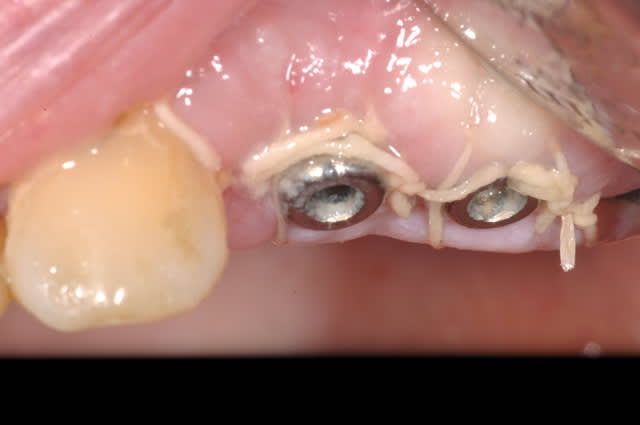

Contrôle à une semaine

est ce que cela répond à ta question?

Dsc 0086 mz7v7v - Eugenol

Dsc 0084 biq0na - Eugenol